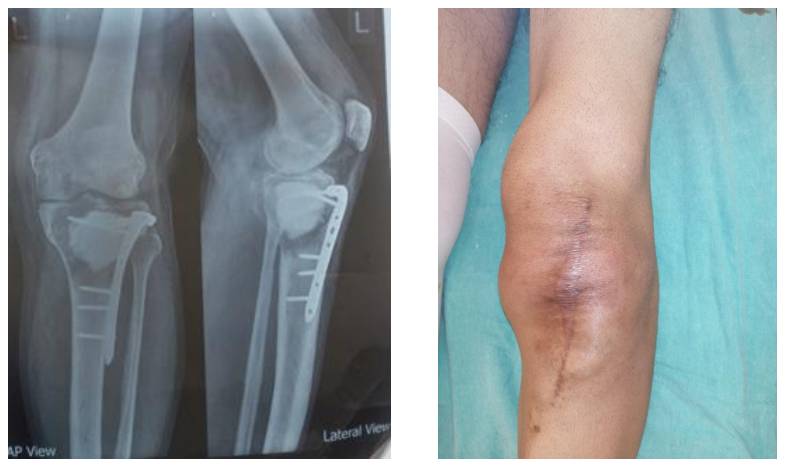

Ameliyat Öncesi: Röntgende proksimal tibiaya uygulanmış olan çimento ve anatomik plak çevresinde litik lezyonlar ile klinik olarak eski insizyon hattı görülmekte.

Ameliyat Sonrası: Röntgende rezeksiyon sonrası uygulanan tümör protezi görülmekte